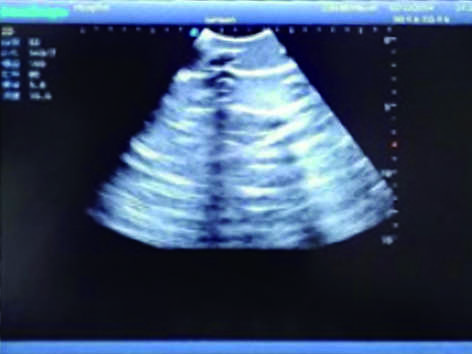

Pneumothorax & Thoracic Closed Drainage Ultrasound Training Model

It is a model covering up from the neck to the umbilicus with body surface markers such as ribs, intercostal space, left and right intercostal arches, armpits and nipples.

2)  Made of high molecular polymer ultrasound material, close to the real skin. It can conduct ultrasound-guided puncture exercises with various clinical models of real ultrasound machines.

3)  Showing clear and real images of the tissues and organs (including muscle and connective tissue, air-containing lung tissue, pleural structure)